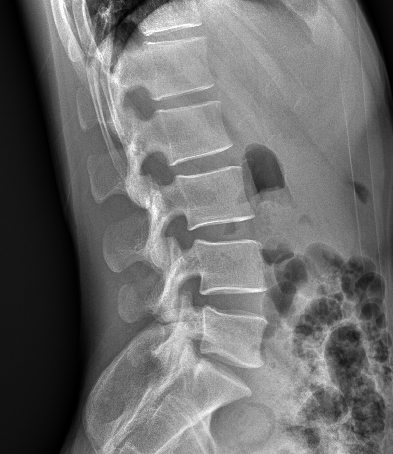

卓越的影像鏈配置是獲得優質影像的有力保障:普利德車載DR采用高頻高壓發生器、大熱容量球管確保穩定、精確的射線輸出;17X17英寸大尺寸無線平板探測器,更大的視野范圍,更高的靜態空間分辨率,確保呈現清晰影像。

同時,多種智能化設計可大幅提升檢查效率。比如,球管與胸片架聯動,方便快捷;腳踏板可縱向移動30公分,患者無需移動就可以完成其他部位檢查;標配AEC自動曝光控制功能,智能控制感光量等。

普利德車載DR可進行胸部等部位的X射線數字攝影檢查,滿足大規模體檢及傳染疾病控制需求,尤其在重大疫情預防等應急檢查工作中具有突出優勢,為各級醫療機構快速應對突發性公共衛生事件提供強大助力,實力護航健康之路。